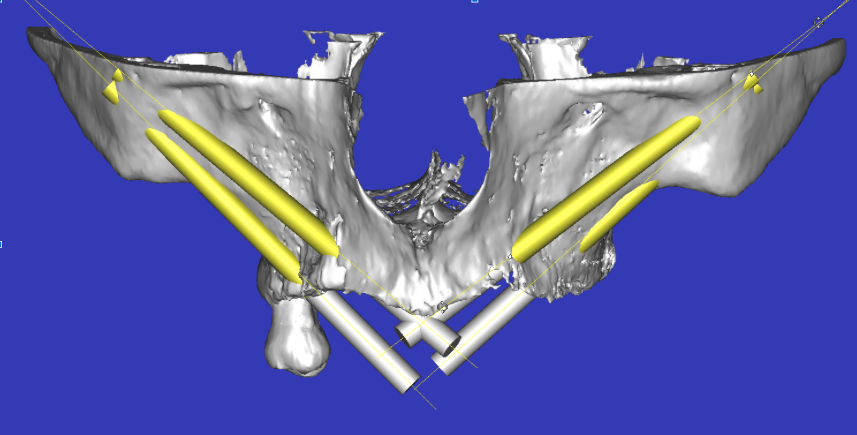

Estructuras Subperiósticas.

Estructura Subperióstica con carga inmediata maxilar

Paciente con atrofia total del hueso del maxilar que precisa rehabilitación. Se le realizó tratamiento con estructura subperióstica y el mismo día se le colocaron unos dientes fijos provisionales sobre la estructura.